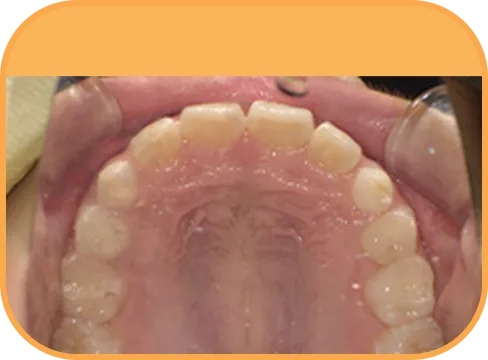

• After

• 上 顎

治療後上顎からの歯の様子

主 訴

上の前歯がねじれている、ガタガタ

治療内容

インビザライン・ファースト

治療期間

8か月

治療費(税別)

450,000円+診断料50,000円

リスク・副作用

• 親知らずの影響や加齢などによって、凸凹が生じる可能性があります。

• 治療の初期段階では痛みや不快感が生じやすくなりますが、1週間前後で慣れます。

• 顎の成長発育によって、噛み合わせや歯並びが変化する可能性があります。

• 状況により当初予定した治療計画を変更する可能性があります。